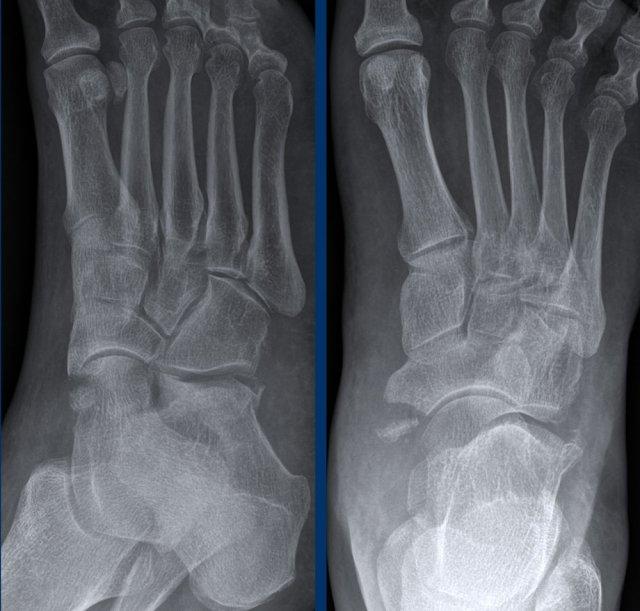

Ca 2 – Đau mạn tính

Bé gái 17 tuổi bị đau mạn tính vùng cổ chân và bàn chân.

Bệnh nhân có tiền sử bong gân cổ chân tái phát nhiều lần.

Hình ảnh cho thấy những dấu hiệu gì?

Nhấp vào hình ảnh để xem phóng to.